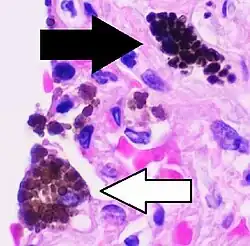

Comparison of pigmented pulmonary macrophages

| Disease | Macrophage name | Macrophage pigment appearance (HE stain) | Usual macrophage location | Associated medical history | Image | Image comment |

|---|---|---|---|---|---|---|

| Chronic pulmonary congestion | Siderophages | Brown-golden and refractile.[5] | Alveoli[6] |

|

Siderophage (black arrow), and interstitium with edema, hemosiderin deposition (black arrow) and collagenous thickening, indicating heart failure. |